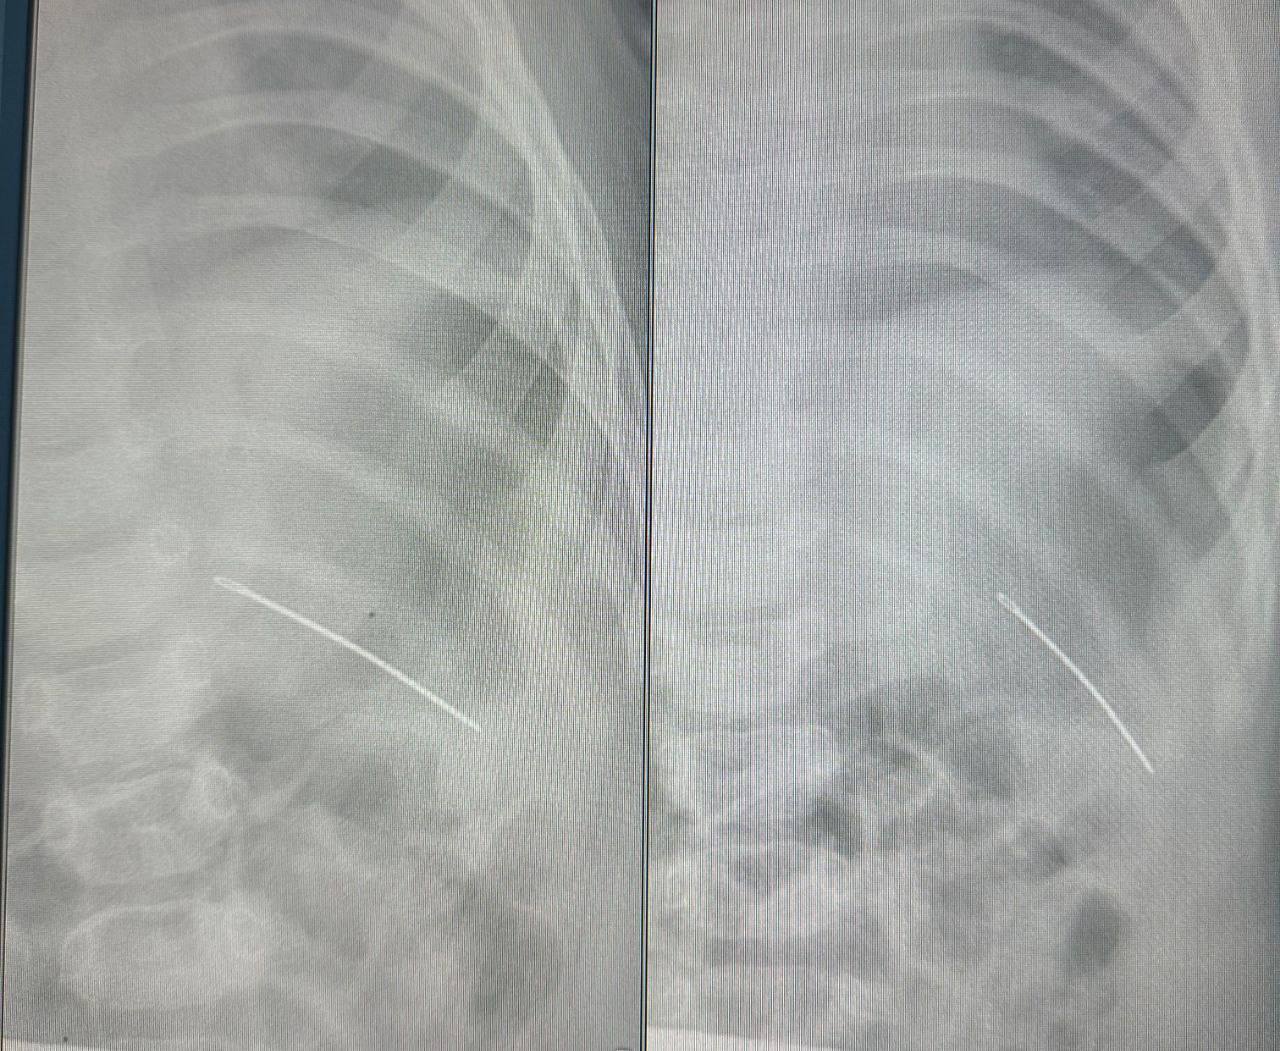

Врачи провели диагностические исследования — рентген ключицы и тазобедренного сустава. По результатам исследования определили, что в грудной клетке ребенка находилась швейная игла. Случай оказался непростым: возможно, в результате падения игла зашла чрез кожу снаружи, проткнув насквозь ребро. В результате чего у девочки были затрудненные движения левыми рукой и ногой. Медицинские работники оперативно приняли решение об операции и безопасно удалили инородное тело, сообщает пресс-служба областного минздрава.

Детский хирург областной клинической больницы Дмитрий Быков отметил, что если бы игла оказалась на 2 сантиметра выше, она могла бы попасть в сердце, что создало бы непосредственную угрозу для жизни.